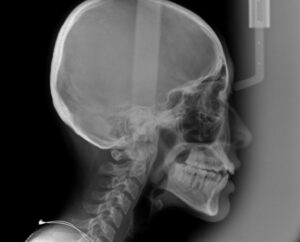

精密検査用の

セファロというレントゲンを撮影

人工知能の結果をもとに

歯科医が治療方針を検討

今回は小臼歯は非抜歯で矯正